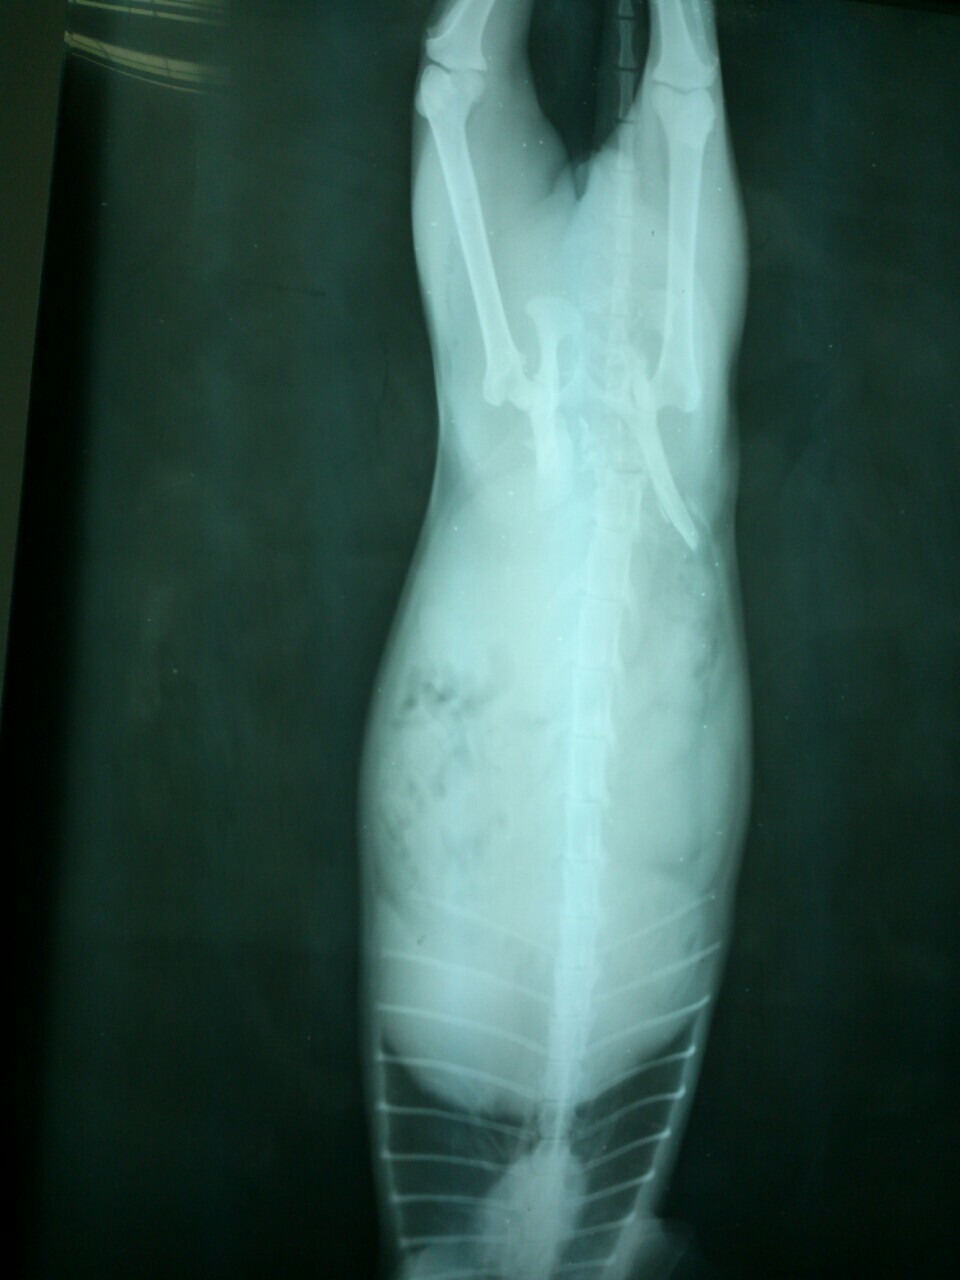

1/19貓咪照X光,確定為骨盆腔錯位碎裂,癱瘓機率非常高!

只能等待骨盆腔骨頭自行慢慢癒合之後再評估做後續醫療,

貓咪無法自行排尿,需要每天早、中、晚幫貓咪擠尿。(可以自行排便)